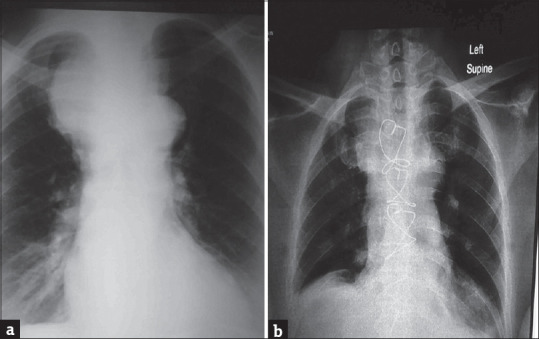

对于由于胸骨后甲状腺肿压迫气管而预期插管困难的患者,存在多种选择。在这种微妙的情况下,选择何种技术来保护气道通常取决于气道阻塞的位置和程度、可用的资源/设施以及麻醉师的经验和偏好。我们报告的情况下,68岁的妇女严重气道阻塞从胸骨后甲状腺肿来全甲状腺切除术。气道管理从清醒光纤插管开始,进行气管切开术,最后在早期技术失败后使用刚性支气管镜获得足够的通气。

A number of options exist for patients with anticipated difficult intubation on account of a retrosternal goiter compressing on the trachea. The chosen technique(s) to secure the airway in this delicate situation often depends on the location and degree of airway obstruction, available resources/facilities, and an anesthetist's experience and preferences. We report the case of a 68-year-old woman with severe airway obstruction from a retrosternal goiter coming for total thyroidectomy. Airway management started with an awake fiber-optic intubation, proceeded to a tracheostomy and finally to use of a rigid bronchoscope following failure of the earlier techniques to achieve adequate ventilation.